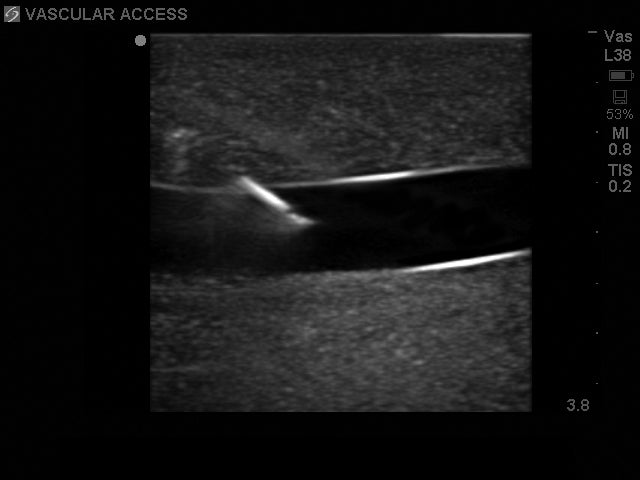

This ultra-durable replacement skin is constructed using Blue Phantom's patented SimulexUS™ tissue technology. Matching the acoustic characteristics of human tissue and designed for repeated use, this central line replacement tissue offers users superb realism at a low cost of ownership. Use with any ultrasound system and experience superior image quality.

This ultrasound simulator provides clinicians with various access points including internal jugular (IJ), subclavian, infraclavicular and supraclavicular approaches as well as access via the axillary vein. The ultrasound central line replacement skin contains vascular anatomy including the internal jugular vein (IJ), brachiocephalic vein, subclavian vein, axillary vein, carotid artery, subclavian artery and axillary artery. The superior vena cava, right atrium and right ventricle offer users the ability to thread guidewires and catheters. This ultrasound replacement tissue also includes internal landmarks such as the trachea, suprasternal notch, manubrium and clavicle. Clinicians can utilize ultrasound guidance for central line placement or use traditional external landmarks for blind central venous access technique.

Users can visualize the pulsatility of the arteries via ultrasound for positive identification of the targeted vessel. Positive fluid flow in the vessels provides clinicians with immediate feedback when the vessels are successfully accessed. The veins are also compressible using mild pressure while the arteries remain uncompressed. Venous and arterial fluid removed from the training model during central line training can be easily refilled by using the provided QuickFill™ ports or and IV bag to continuously refill the vessels.